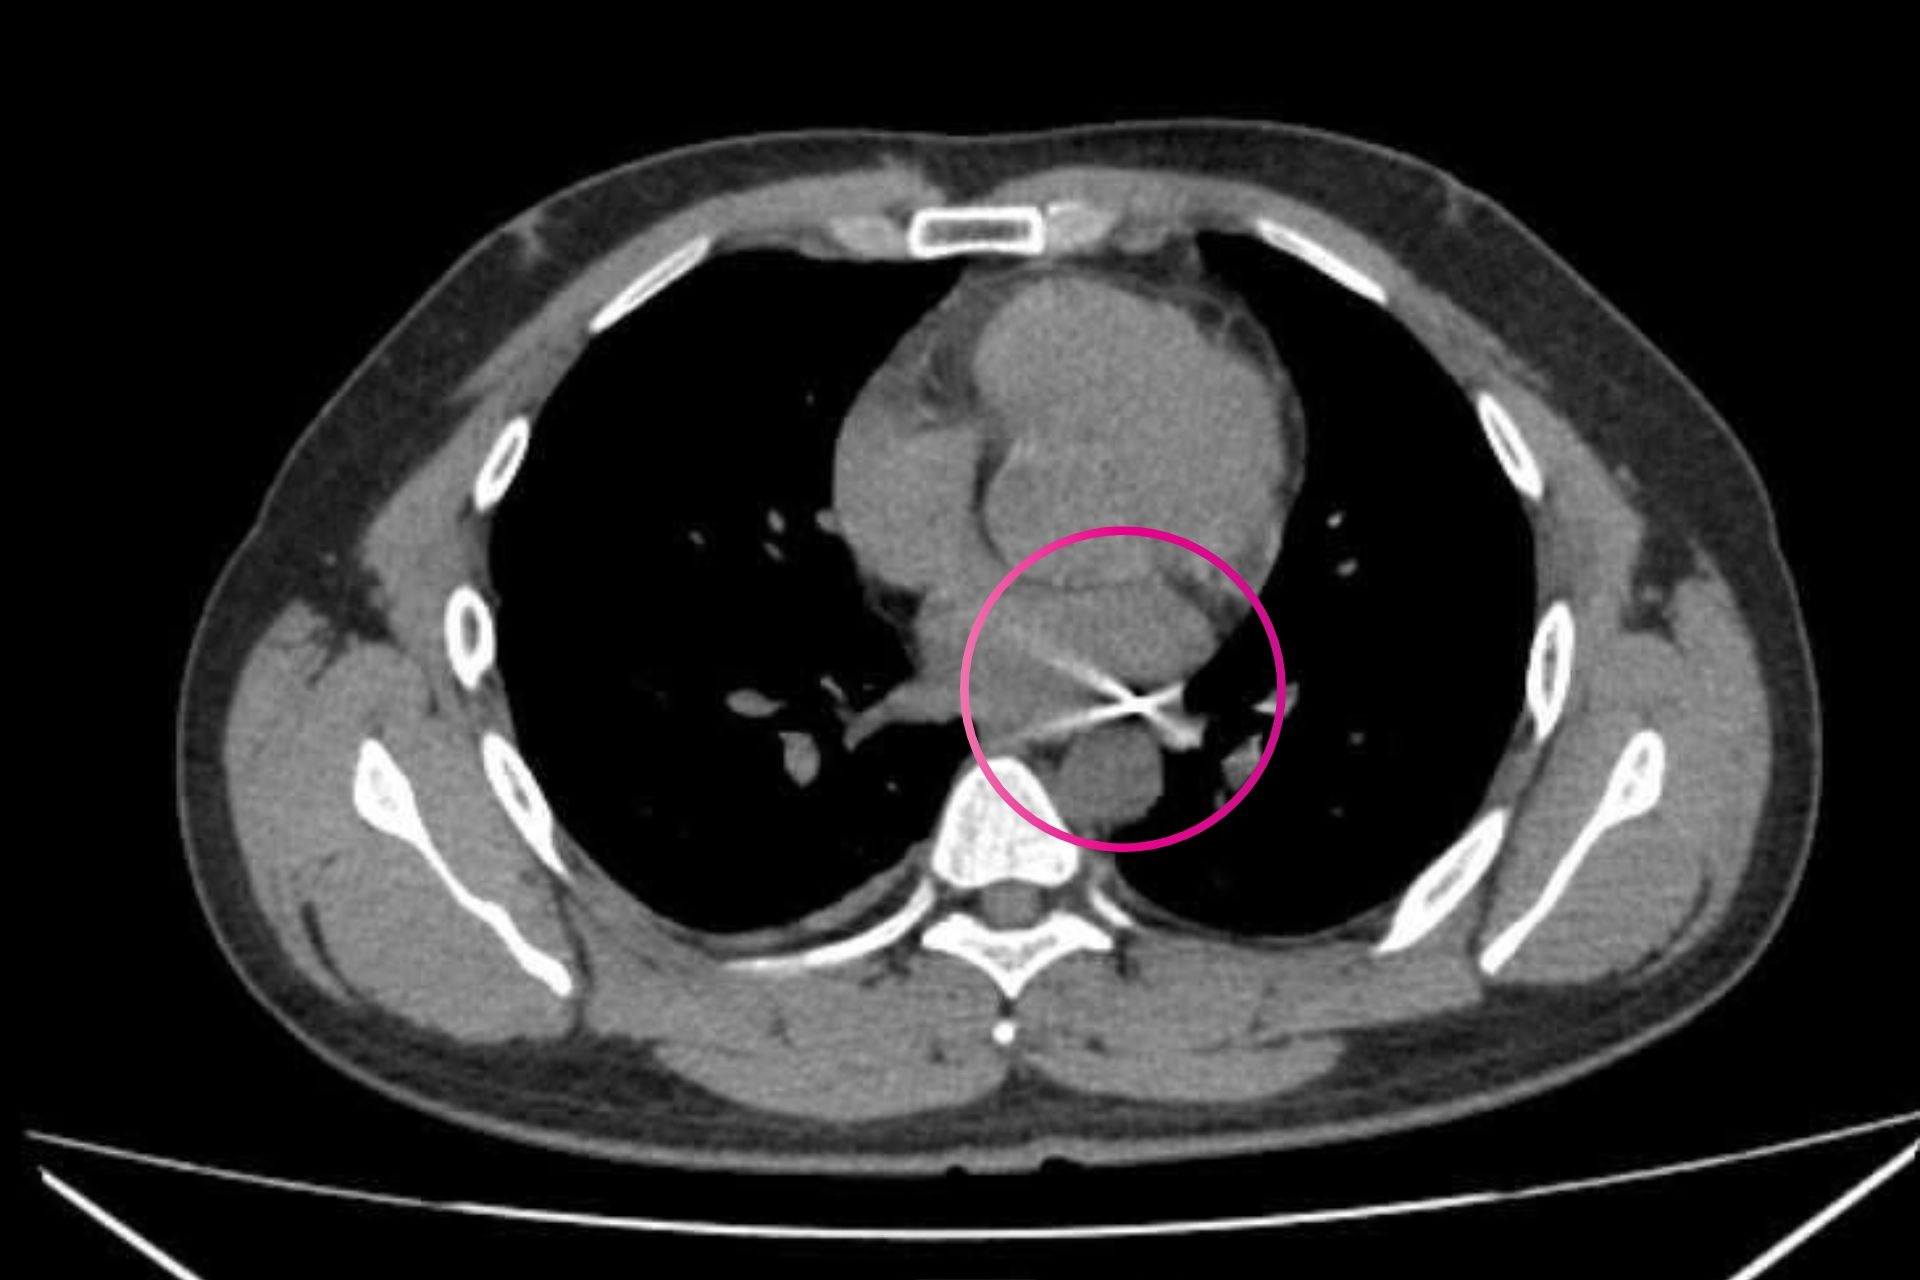

Ngay khi tiếp nhận, ê-kíp trực lập tức triển khai các biện pháp hồi sức khẩn cấp như ép tim ngoài lồng ngực, đặt nội khí quản để cung cấp oxy trực tiếp vào phổi, đồng thời sử dụng thuốc vận mạch nhằm tăng sức co bóp cơ tim. Sau khoảng 10 phút cấp cứu liên tục, bệnh nhi đã có nhịp tim trở lại.

Bác sĩ Trần Lê Duy Cường, Phó khoa phụ trách Khoa Hô hấp cho biết, sau khi có lại tuần hoàn, bệnh nhi tiếp tục được hồi sức tích cực, sử dụng kháng sinh, chống phù não và hỗ trợ dinh dưỡng. Sau 24 giờ theo dõi sát sao, tri giác bệnh nhi cải thiện rõ rệt và đã được rút ống nội khí quản.